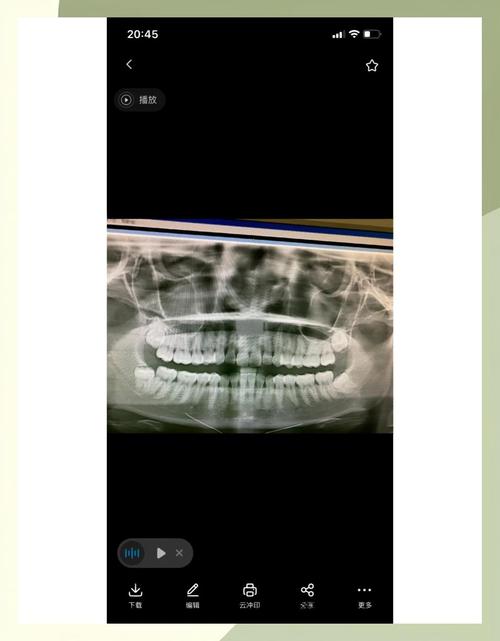

- 医生会进行临床检查,并拍摄全口曲面断层片(OPG)或CBCT(锥形束CT),这是评估智齿位置、方向、与邻牙及重要解剖结构(如下牙槽神经管)关系的金标准。